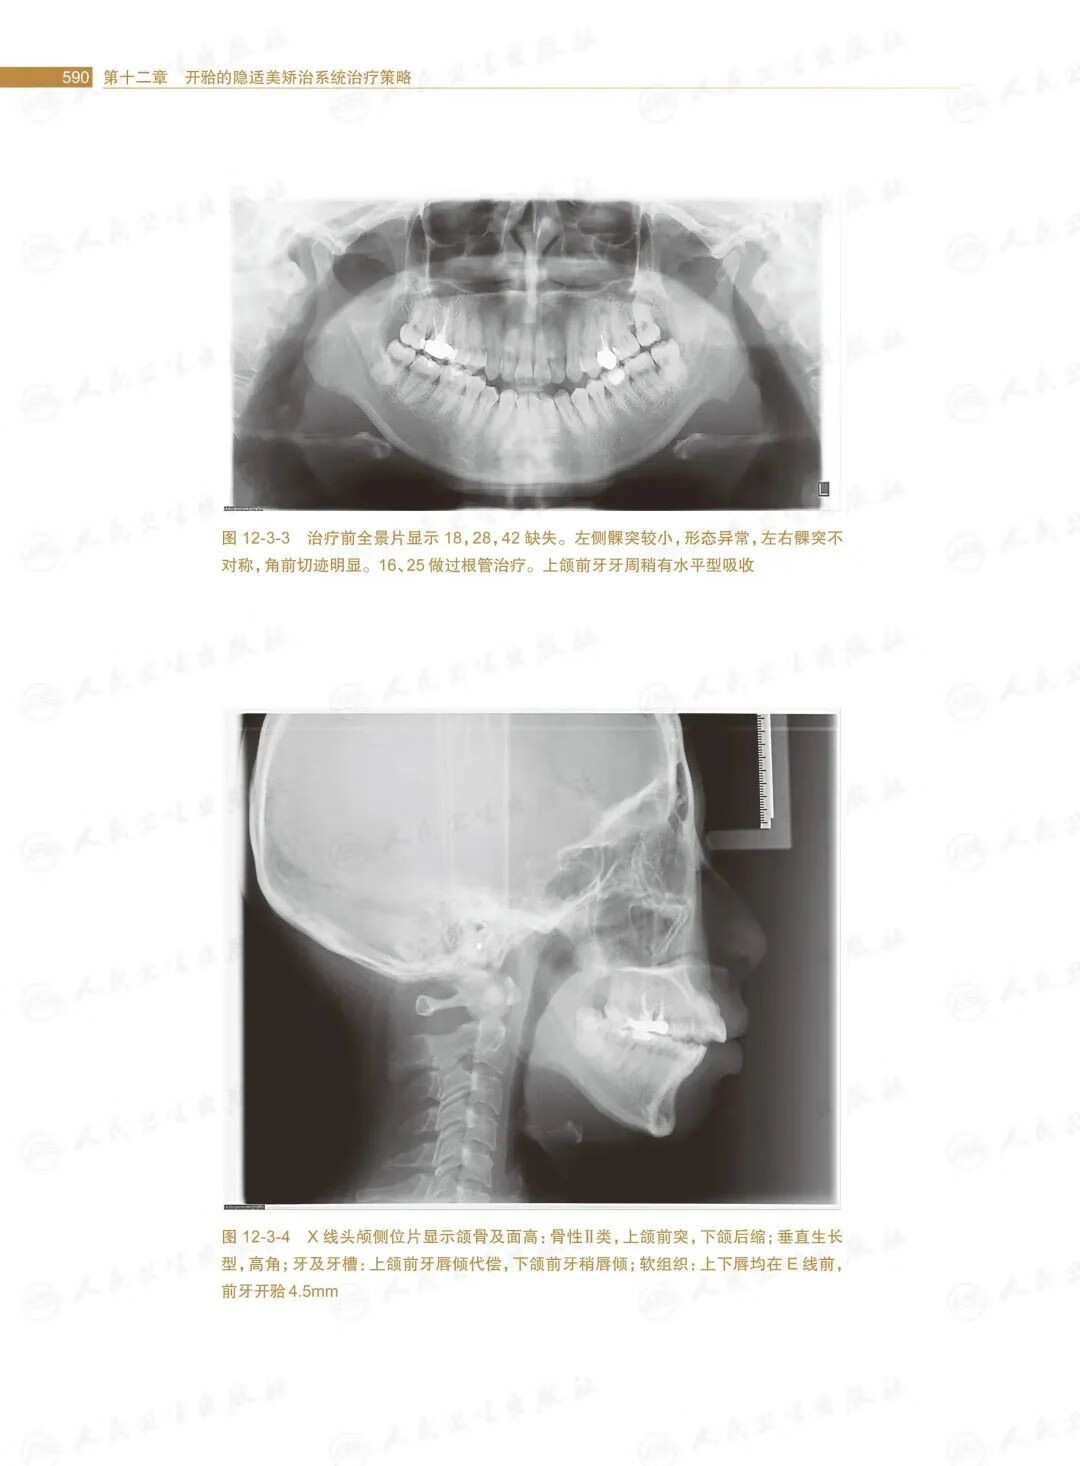

第十二章開的隱適美矯治系統治療策略/.569

第三節安氏Ⅱ類開的矯治策略/588

第四節安氏Ⅲ類開的矯治策略/601